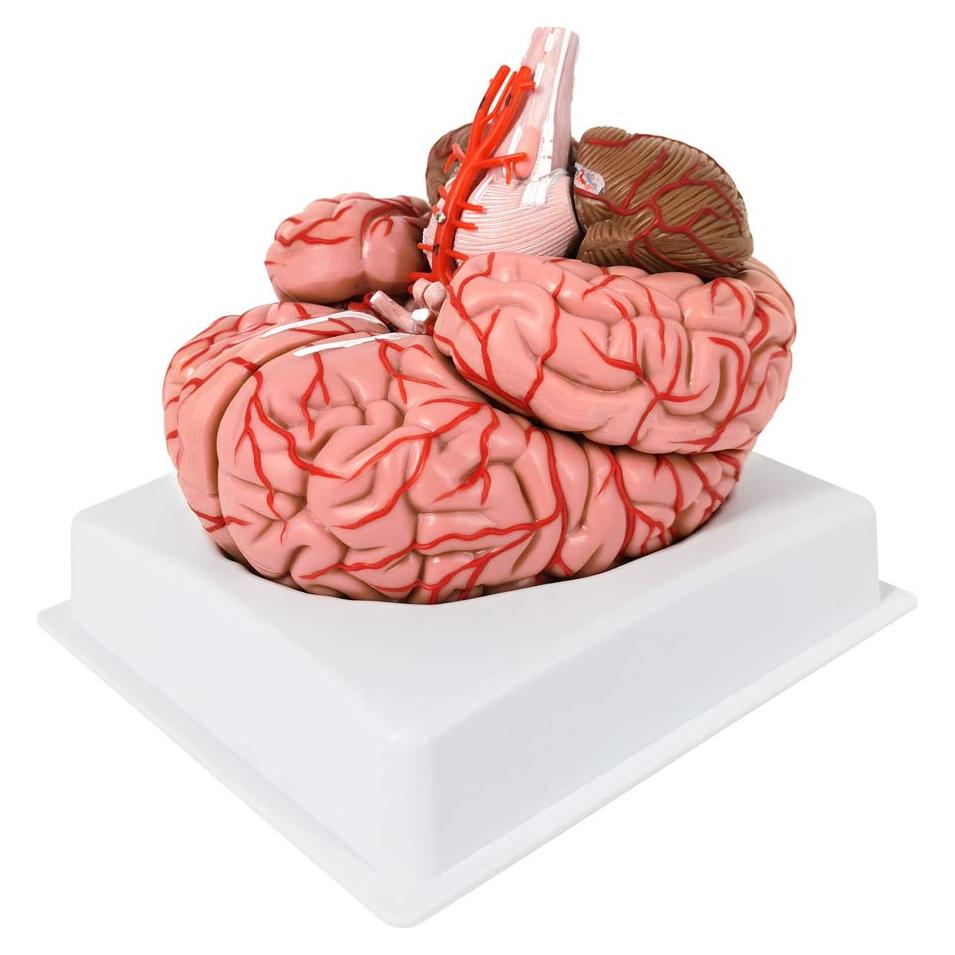

Modelos Anatómicos de Órganos marca Evotech (20 productos)

Modelos Anatómicos 3D EVOTECH SCIENTIFIC - Cuerpo, Corazón y Esqueleto